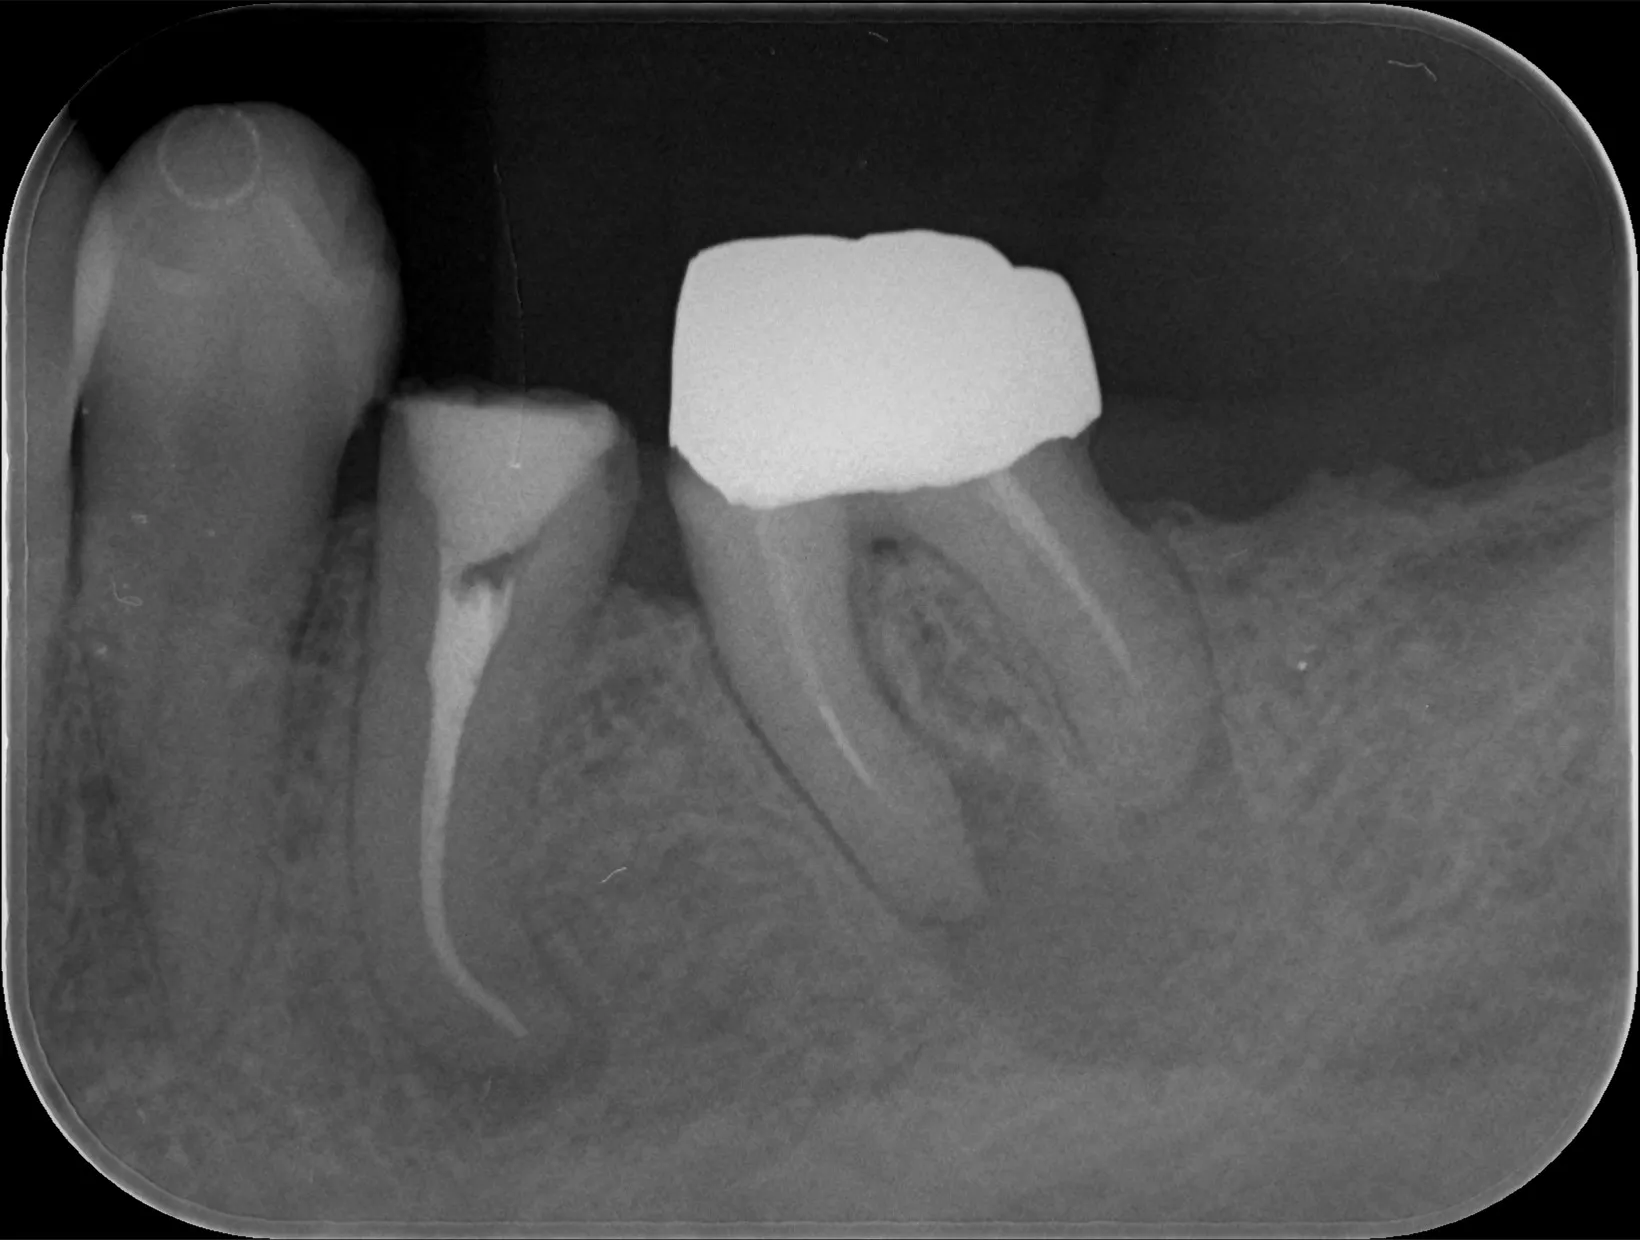

レントゲン画像

右から2番目の歯

レントゲン画像の右から2番目の歯は白い像があり金属の土台が入っている状態で、治療途中になっている歯の継続治療を希望されました。

レントゲン撮影を行わなければおそらくそのまま被せ物の型どりを行って終わりになっていた歯ではありますが、レントゲン撮影を行うと歯根は根尖部で彎曲し、先端部分では黒い影が写っています。

これは歯を支えている骨が溶かされている像で、多くの場合には根尖部に膿が溜まってしまっている状態です。

原因は歯の根っこの中に汚染物質がありそこに細菌が住み着いていることによって根尖方向に膿が出ていき溜まってしまっていることです。

ちなみに更に右に写る歯の根っこの先にも黒い像が写っており同じく膿が溜まってしまっていると思われます。

この状態では継続治療として被せ物を作って終わりというわけにはいかず、金属の土台を外して根っこの治療(根管治療)を行っていくこととしました。